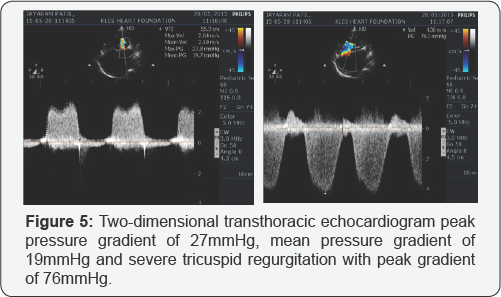

The electrocardiogram (ECG) showed sinus tachycardia with rightaxis deviation (+110°), left atrial enlargement and right ventricular hypertrophy (RVH) (Figure 1). The chest x-ray showed evidence of left atrial enlargement, pulmonary venous hypertension and pulmonary arterial hypertension (Figure 2) . The two-dimensional transthoracic echocardiogram (TTE) revealed thickening and shortening of the anterior and posterior mitral leaflets and chordae, fusion of the commissures with anterior leaflet doming and fixed posterior mitral leaflet (Figure 3) , turbulent mitral inflow jet, severe subvalvular stenosis with peak pressure gradient of 27mmHg, mean pressure gradient of 19mmHg and mitral valve opening of 0.35cm2 by planimetry (Figure 4). The patient also had severe tricuspid regurgitation with peak gradient of 76mmHg (Figure 5) and severe pulmonary hypertension, estimated right ventricular systolic pressure 91mmHg. With all these echocardiographic evidences and clinical condition of congestive cardiac failure, a diagnosis of severe MS and severe pulmonary artery hypertension (PAH) was concluded. The patient clinical condition was initially stabilized by strict bed rest and decongestive therapy with diuretics. After intial stabilization the patient was taken for commissurotomy.